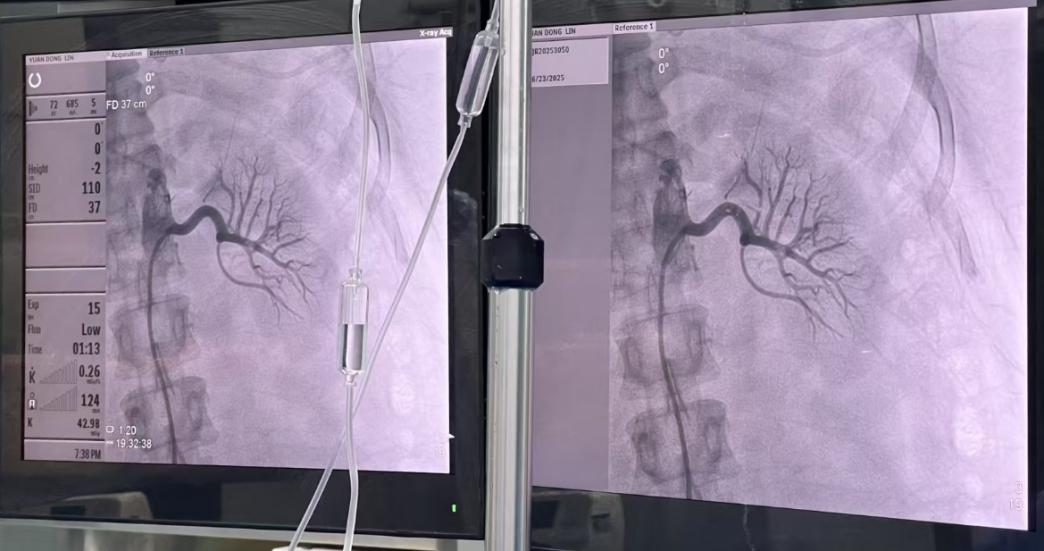

住院期间,高玲医生和周从良医生为她安排了全面的继发性高血压筛查及目前靶器官损害的筛查,护理团队也给她做了详细的健康指导。最后综合评估下来,确定小袁是“难治性高血压(原发性)”。因为小袁服用多种药物多年不能达标,且年纪轻,心率偏快,肾功能还好,医生们经过讨论,认为可以做一种叫做“经肾动脉去交感神经术(RDN)”的介入治疗。在充分沟通后,小袁和家人同意了这个方案。

医生为小袁实施经肾动脉去交感神经术(RDN)

随后,在华西教授的指导下为小袁实施了经肾动脉去交感神经术(RDN),手术顺利。术后小袁血压明显下降,出院后小袁口服降血压药物种类减少,血压也比以前稳定很多。现在,她仍然定期回到门诊复查,继续管理着自己的血压。